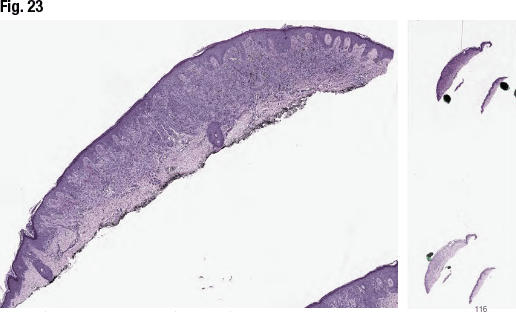

[dropcap]I[/dropcap]n closing, Dr. Aung presented the case of a 20-year-old female with a brown lesion on the thigh that was enlarging and becoming darker. Asymmetrical compound melanocytic proliferation is seen in Fig. 23. In high power the cytologic atypia with Spitzoid features, lack of maturation with dermal descent, and irregularly dispersed deposits of melanin pigment are seen (Fig. 24). In Fig. 25: marked cytologic atypia, showing some of the cells with prominent nucleoli, and mitotic activity at the deeper portion of the lesion. MART-1/Ki67 showed scattered proliferative cells in the dermis and there was patchy expression with HMB-45. “We also performed FISH, which was negative,” she said.

The consensus diagnosis (five to two) among Dr. Aung’s group favored the diagnosis of melanoma with Spitzoid features, she said, primarily based on prominent cytomorphologic atypia, lack of maturation, and presence of a deep dermal mitosis (close to the base of the lesion), despite the negative FISH result.